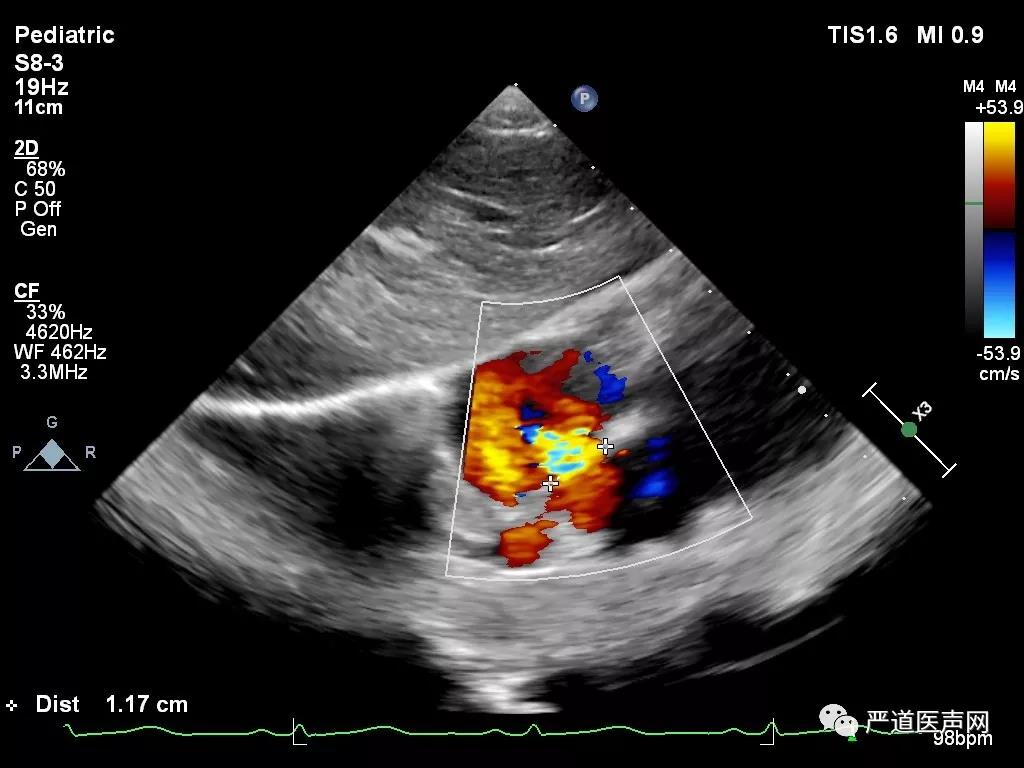

经胸超声心动图提示:右心房增大,房间隔缺损多个切面测量最大直径约12mm(胸骨旁心尖四腔心、大动脉短轴和剑突下四腔心等),患儿具备手术干预指征,选择进行经皮房间隔缺损封堵术,而此次病例的亮点,张智伟教授团队将使用“全球首创”具有自主知识产权的已获中国药监局批准进入临床试验的可吸收房间隔缺损封堵器(Biodegradable ASD closure Device)。

术前超声测量

术中超声显示:房间隔缺损,继发孔型,大小12mm,右心导管检查提示Qp/Qs:1.45,肺动脉压力28/9 (18)mmHg,建立钢丝轨道,选择6F MPA2导管,经房间隔缺损送入左房,置于左上肺静脉,并导入输送钢丝0.035/260cm。

超声心动图提示伞盘位置良好无残余分流后,进一步逆时针旋转控制手柄,解脱输送钢缆和封堵器栓头的连接,释放封堵器。

术后经胸超声心动图提示封堵器位置稳定,房间隔分流消失,封堵器不干扰心脏瓣膜等心内结果,手术效果满意。